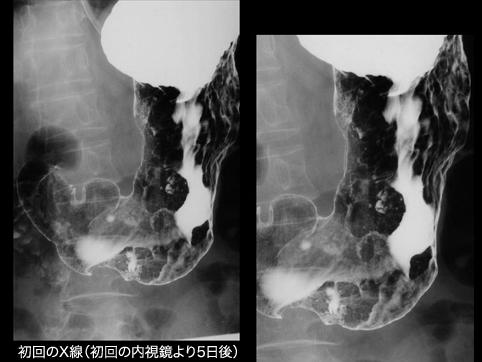

Gastritis Hipertrófica a semejanza de la Linfoma Maligna (Enfermedad Menetrier)

[Image-ID:11151]

Rayos X

30 - 34